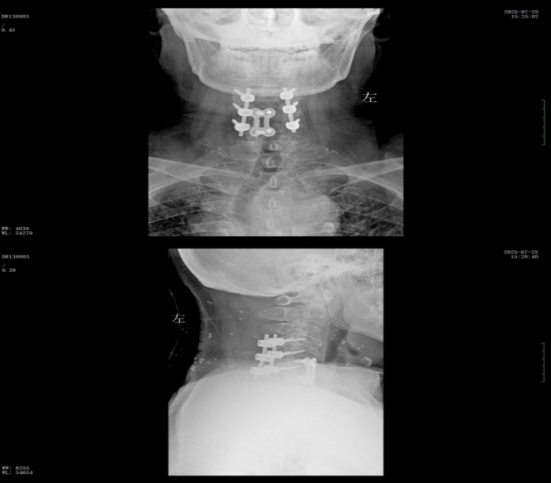

經過精準手術和術后系統(tǒng)的康復治療,患者神經功能得到明顯恢復,四肢肌力及感覺逐步改善,術后肌力達到IV級左右。復查X線顯示內固定位置理想,患者非常滿意。出院之際,患者及家屬對衡陽市中心醫(yī)院的醫(yī)療技術、護理服務及醫(yī)聯(lián)體轉診效率均給予高度評價。

術后x線內固定位置理想